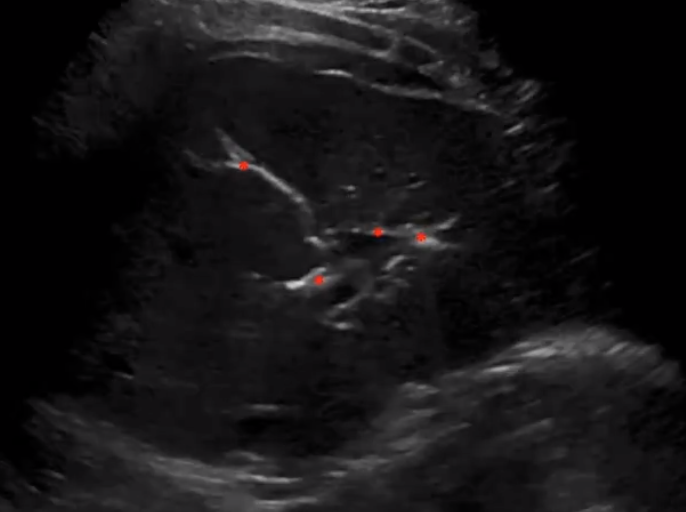

• On US can differentiate from vessels by putting on doppler

• Biliary ducts will have no flow

Pneumobilia

• US

• Linear hyperechoic structures

• Dirty shadowing